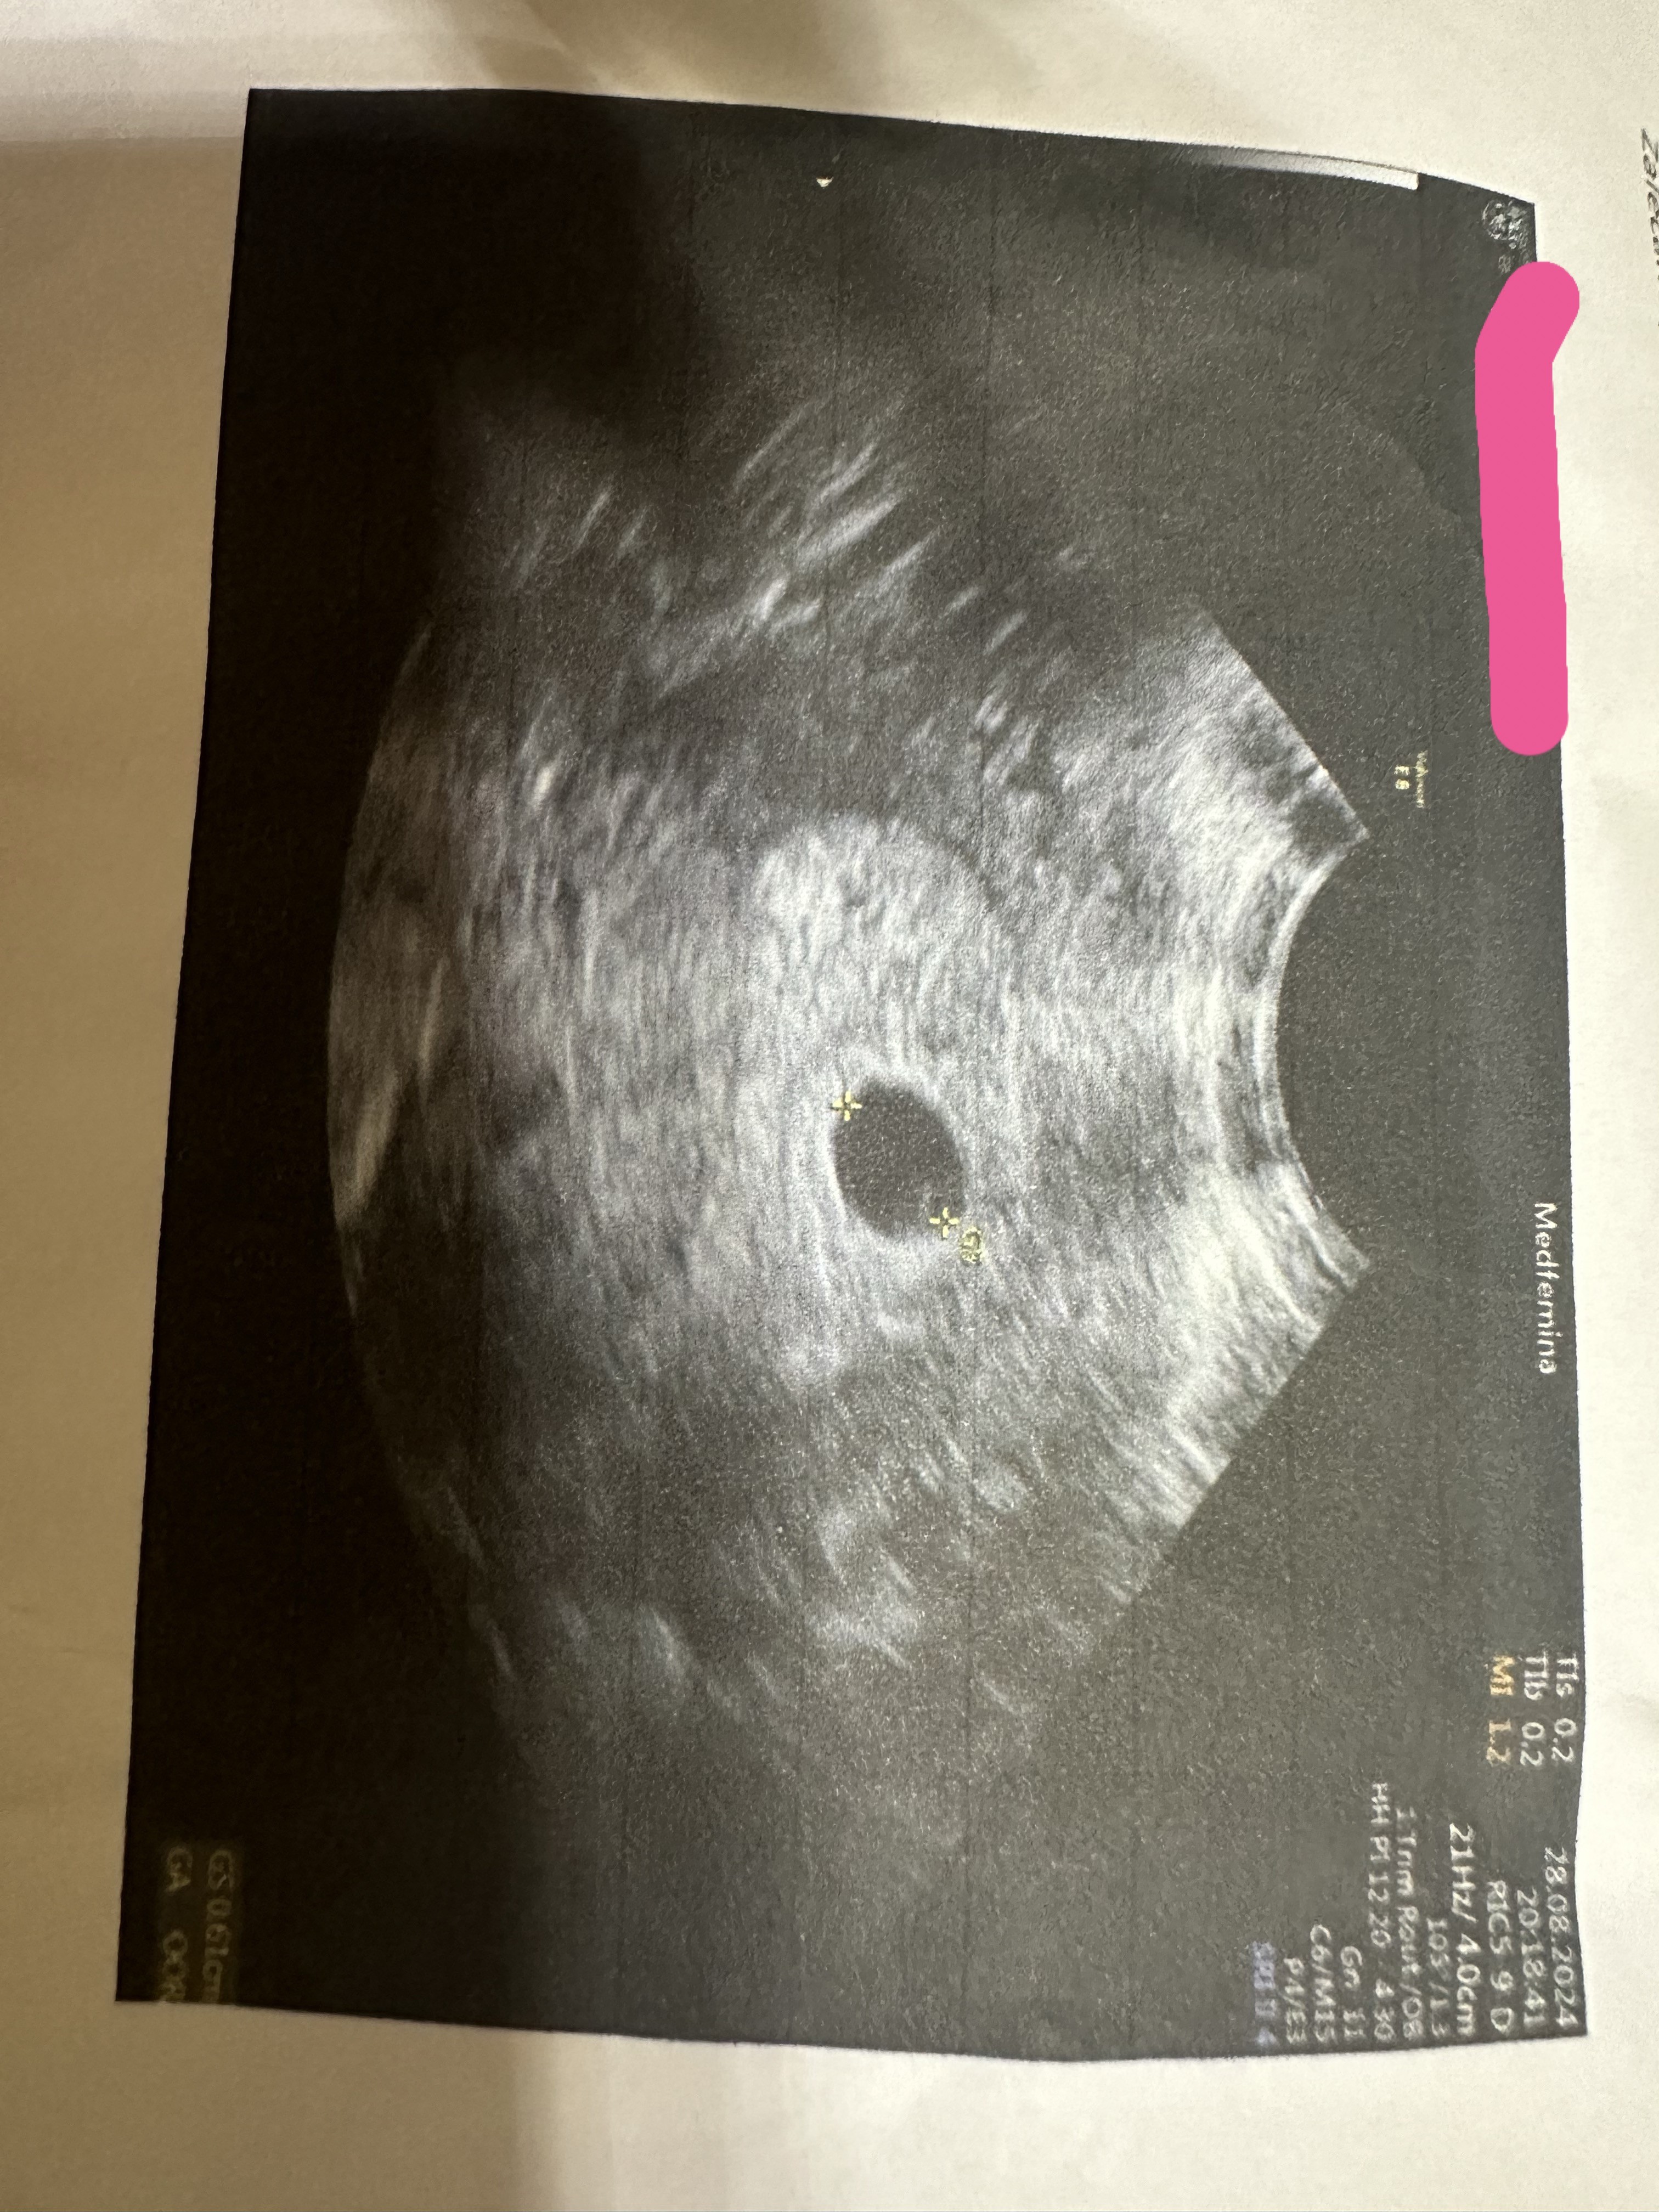

Jestem po 3 poronieniach… obecnie jestem w ciąży (wg ostatniej miesiączki 5t 4d). Przyjmuję zastrzyki neoparin i duphaston. Oczywiście już schodki… lekarz mi powiedział, że USG wygląda na 5t2d.. ale dla mnie, po moich doświadczeniach, ten pęcherzyk jest za mały nawet jak na 5t2d… myślicie że coś z tego może być? Kazał mi przyjść za tydzień, żeby zobaczyć czy prawidłowo rośnie… zastanawiam się czy iść jutro i w sobotę na betę… ale jakoś zle przeczucia mam…